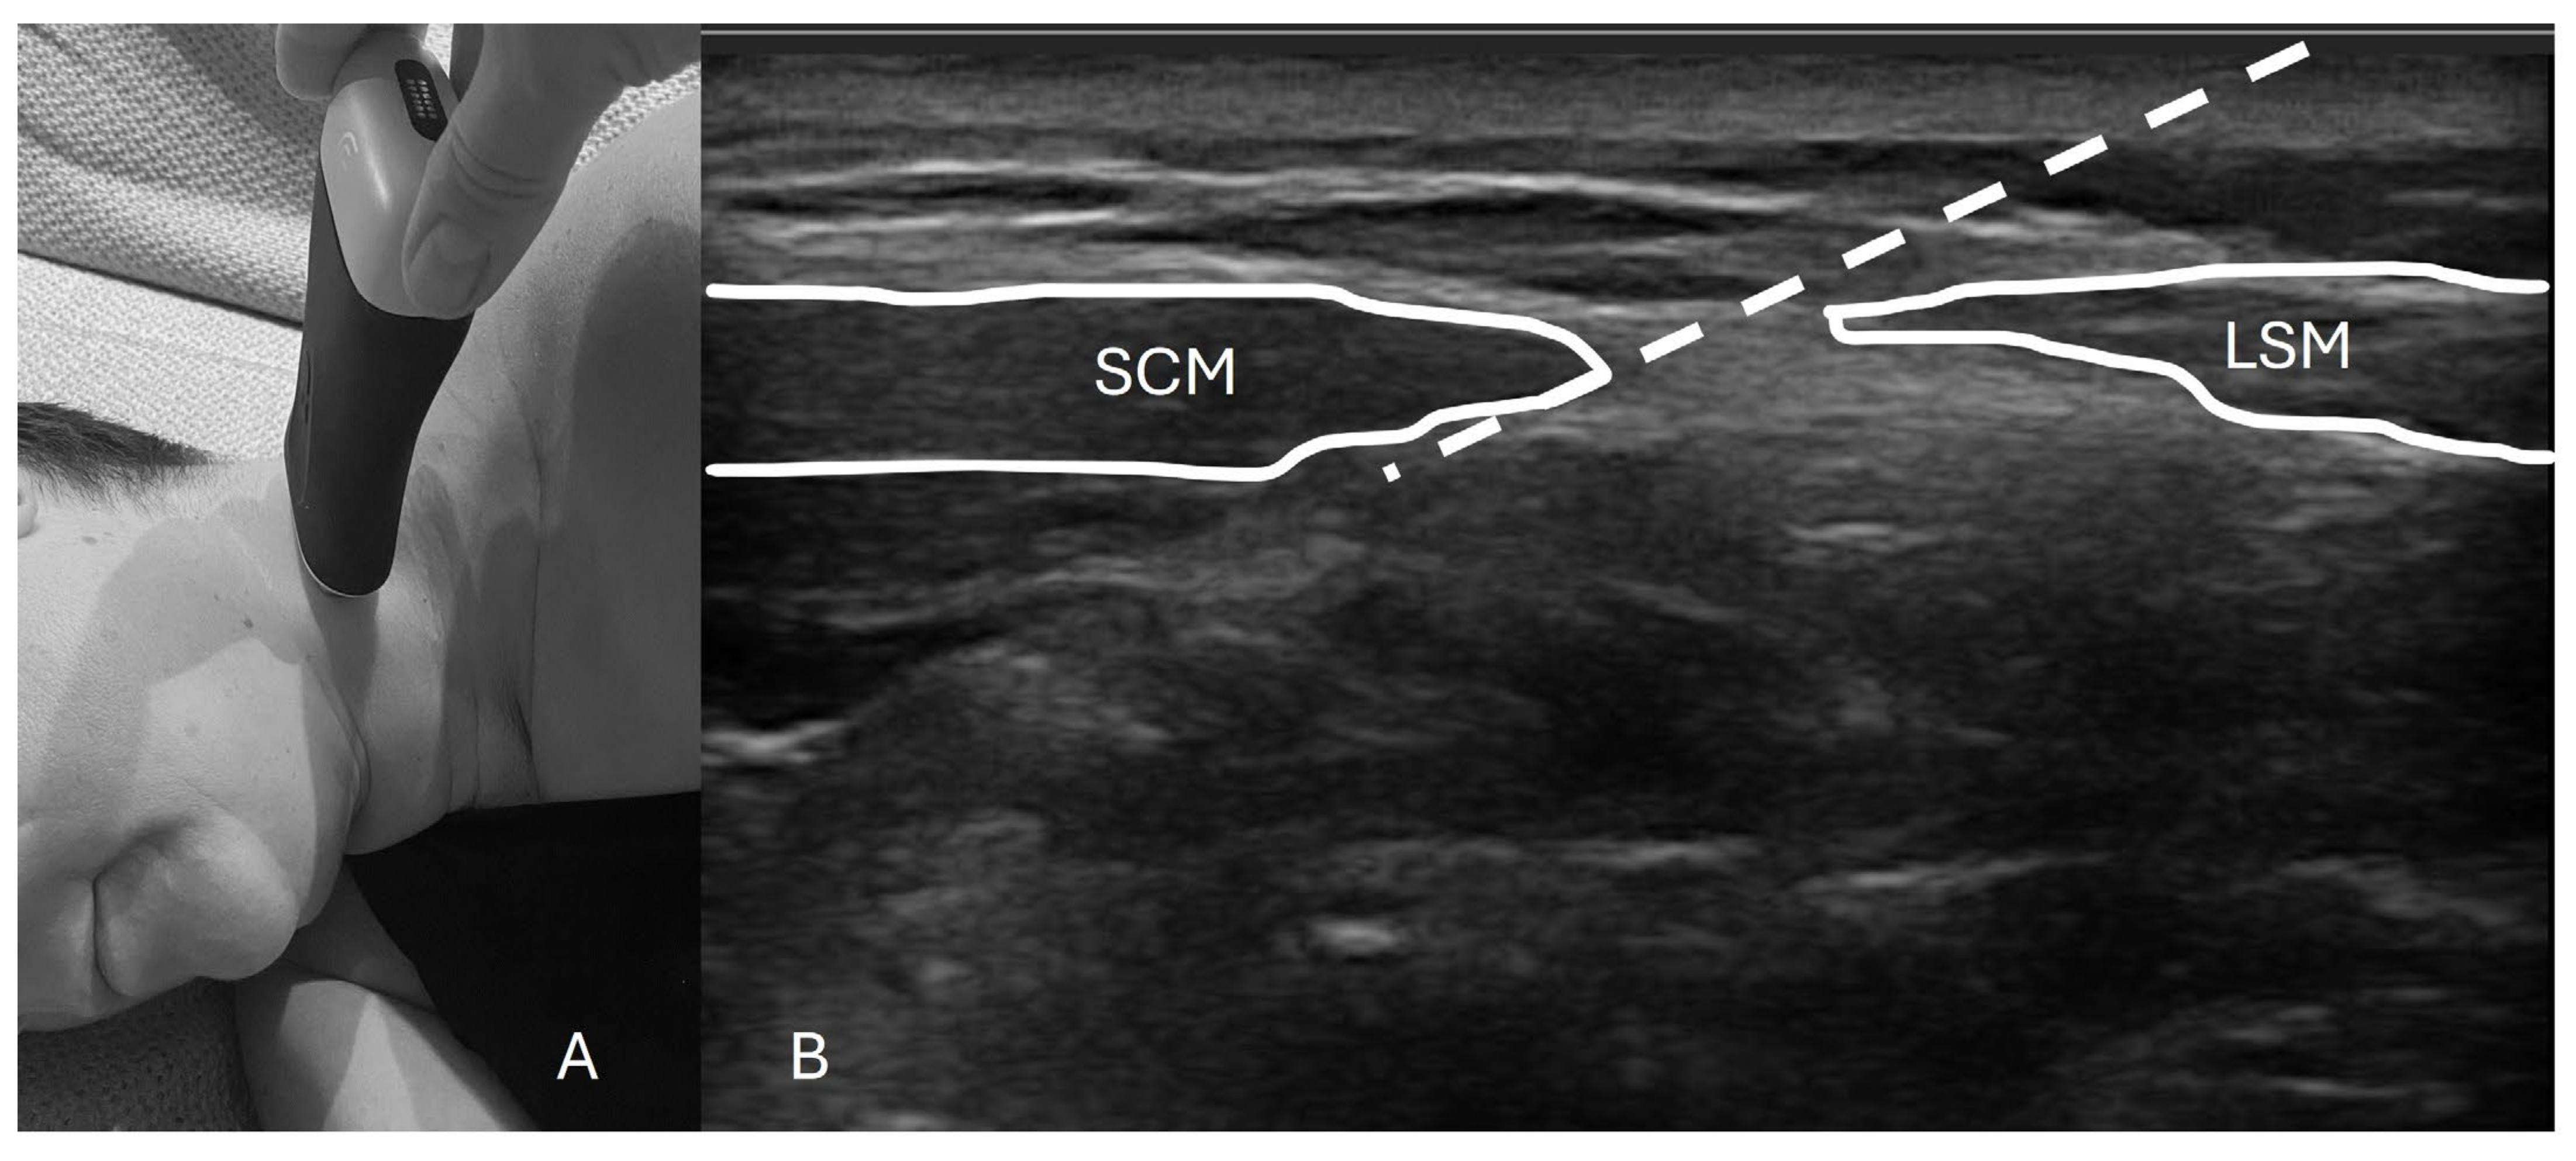

To perform this technique, one must first identify the posterior border of the sternocleidomastoid (SCM) muscle extending from the mastoid process (most cranial insertion of the SCM) all the way down to the lateral projection of the C6 vertebrae. The US probe should provide an axial cut of the neck at the midpoint of the line of the SCM to a height close to the cricoid cartilage. With an “in-plane” approach, the needle is inserted and lands no more than 1 to 2 cm antero-medially under the SCM (Figure 1). After negative aspiration, a volume of local anesthetic is deployed underneath the SCM anterior to the levator scapulae muscle while being careful not to pierce through the prevertebral fascia [5,7]. Figure 1 shows an example of a typical setup for this procedure.

Figure 1.

Probe placement and ultrasound image with landmarks. (A) The patient is positioned in the lateral decubitus position with the ultrasound probe placed approximately at the middle third of the sternocleidomastoid muscle (SCM). (B) An axial ultrasound scan of the cervical area shows the SCM and levator scapulae muscle (LSM). The white striped line indicates the needle trajectory, with the final dot marking the anatomical target for the injection.